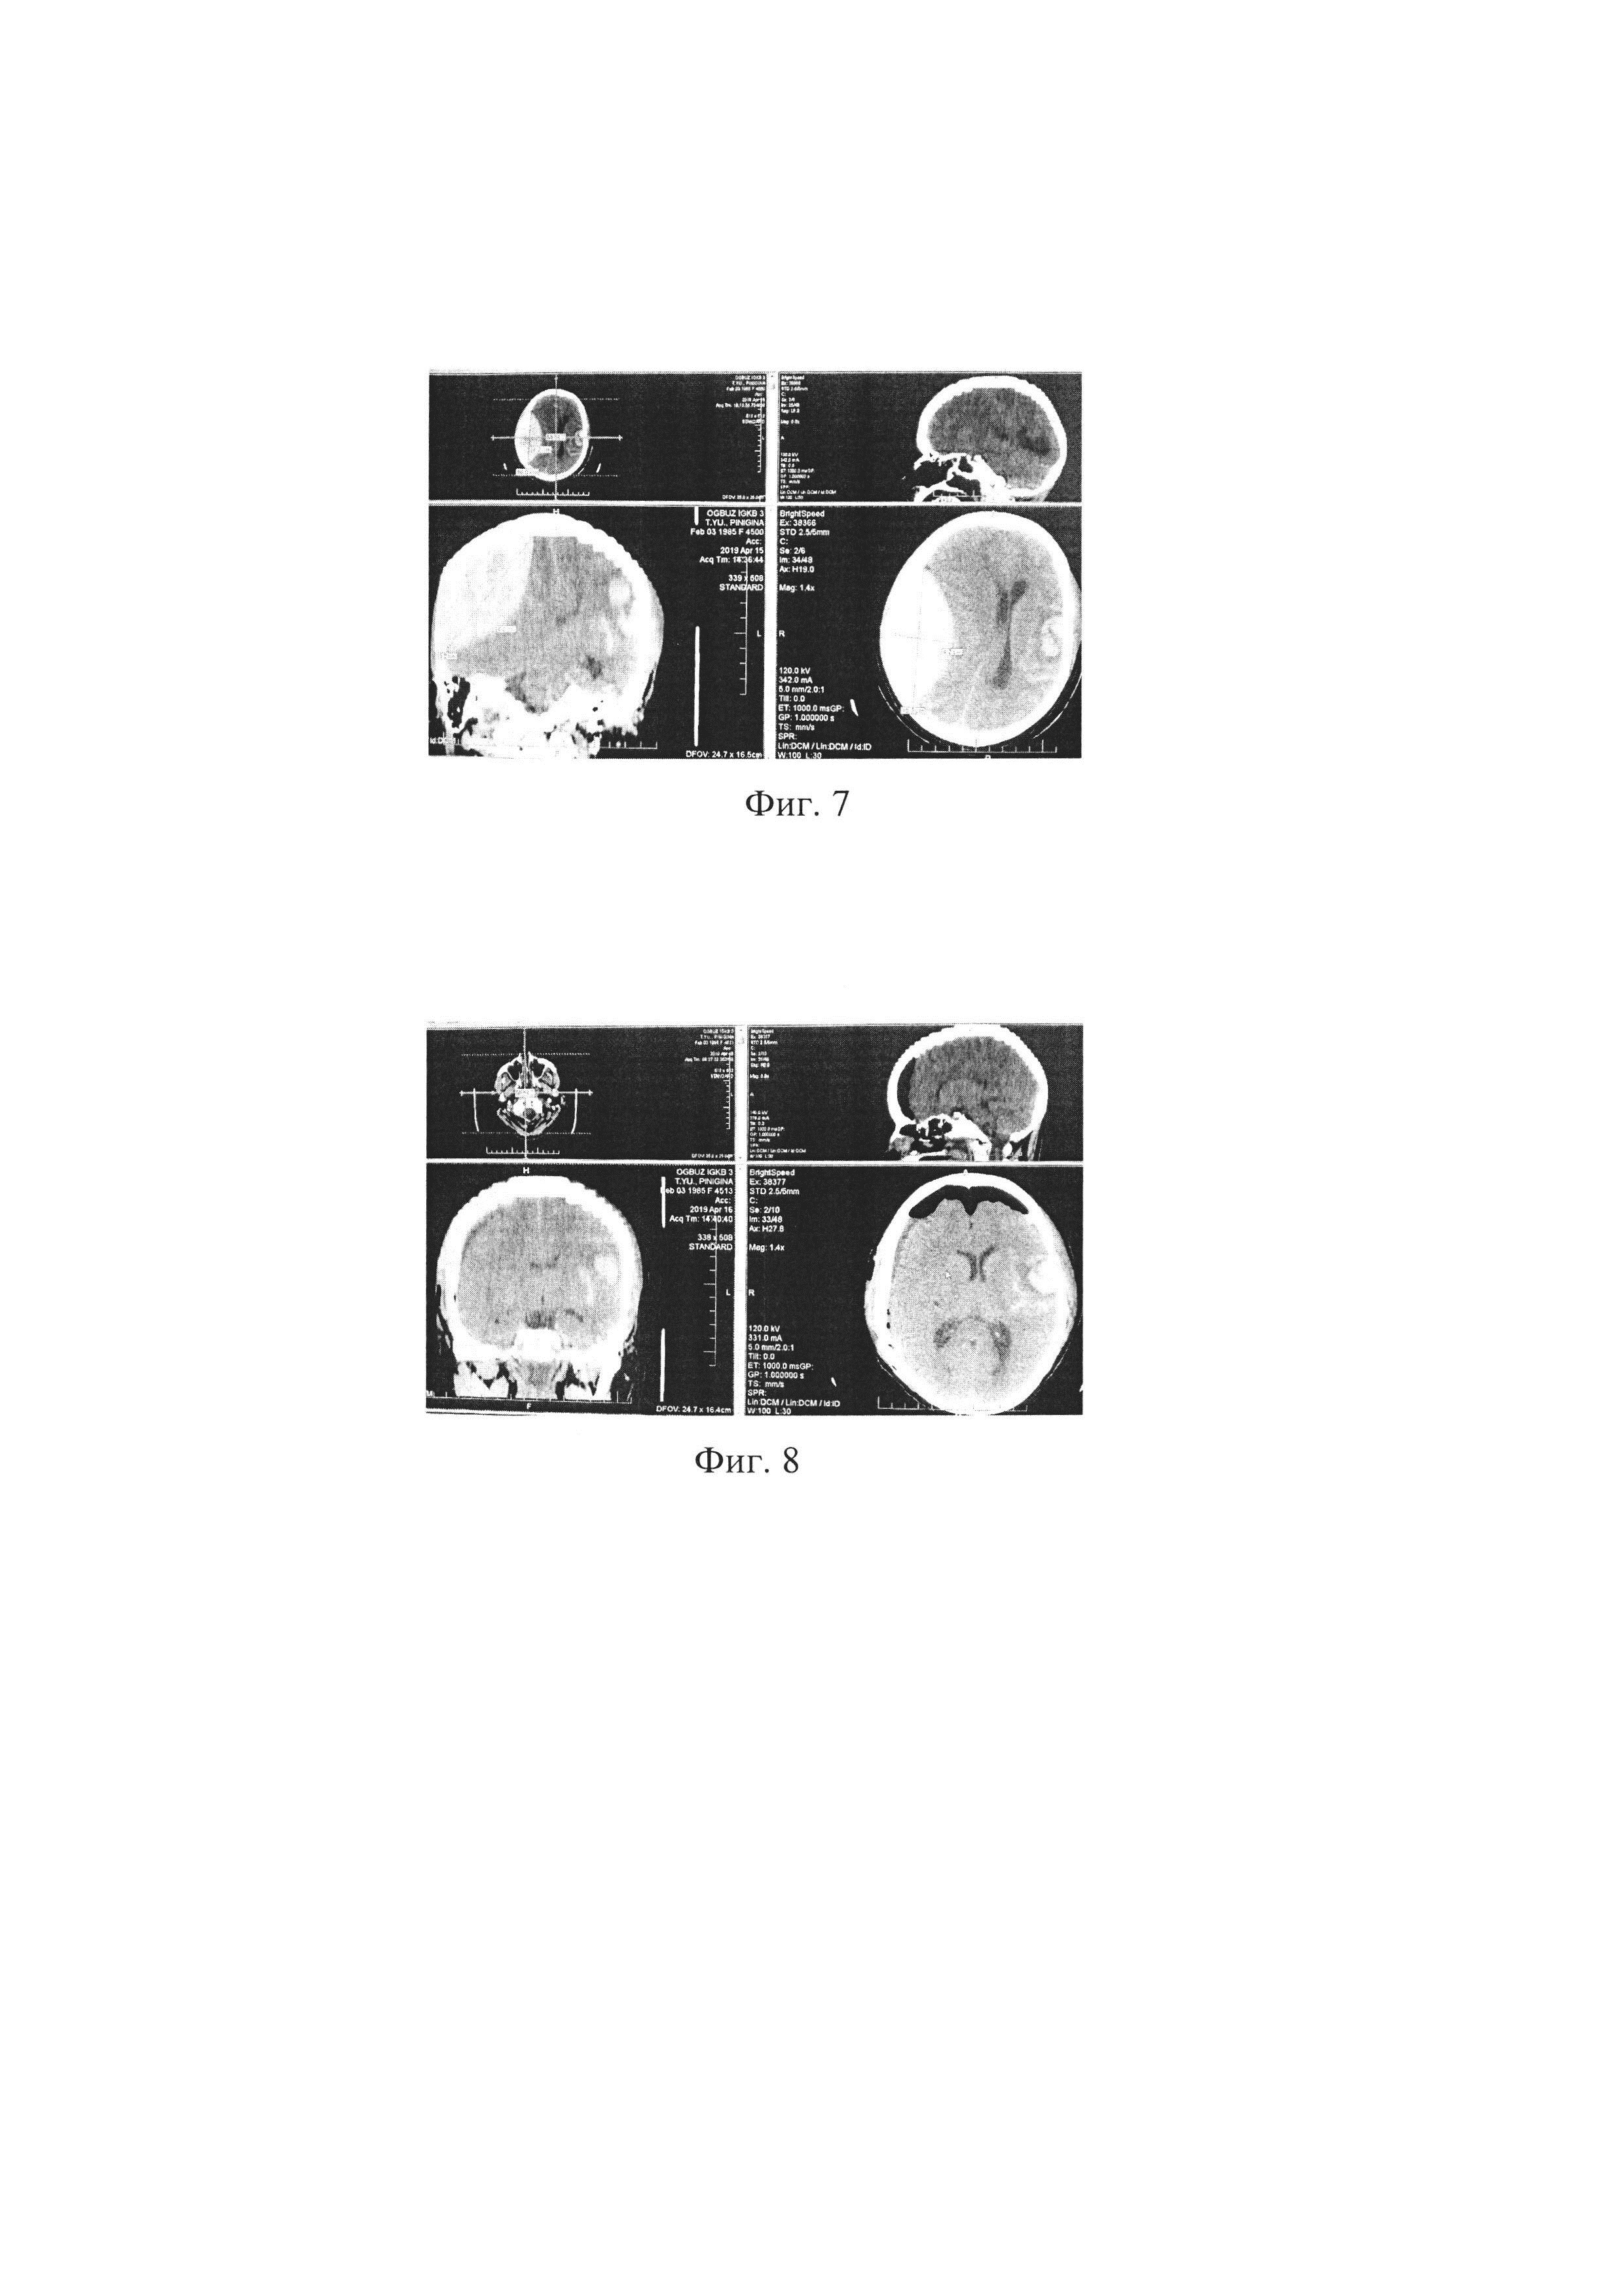

При поступлении выполнена МСКТ головного мозга. Заключение: острая эпидуральная гематома (ОЭГ) правой лобно-теменной области; выраженная дислокация срединных структур с признаками вклинения; контузионные очаги левой лобной доли 3 типа, левой височной доли 2 типа; субарахноидальное кровоизлияние лобных и височных долей с обеих сторон, левой теменной доли; кровоизлияние по намету мозжечка слева; деформация желудочковой системы (фиг. 7).

[72]

Диагноз клинический: ЗЧМТ, ушиб головного мозга тяжелой степени со сдавлением ОЭГ справа; субарахноидальное кровоизлияние; дислокационный синдром.

[73]

При анализе МСКТ исследования установлен объем гематомы - 200 мл; РГХЯ=9 мм; ДОЗН справа равен 4 мм, ДОЗН слева равен 4 мм, ДОЗНср.=4+4/2=4 мм;

[74]

ОВИ=4×100/9=44,4% (т.е. меньше 53,9%) - риск развития гипотензивной реакции головного мозга по типу коллапса. Пациентке по жизненным показаниям выполнена КПТ, удалена ОЭГ. Во время операции ревизия эпи- и субдурального пространств, отмечена «гипотензивная» реакция мозга в виде его «западения». На 2 сутки после КПТ и удаления ОЭГ у пациентки П. отмечена «гипотензивная» реакция мозга по типу коллапса с образованием пневмоцефалии (фиг. 8).

[75]

В послеоперационном периоде пациентка с положительной динамикой, на 5 сутки переведена в отделение нейрохирурги с регрессом неврологической симптоматики. Выписана на амбулаторное лечение в удовлетворительном состоянии.